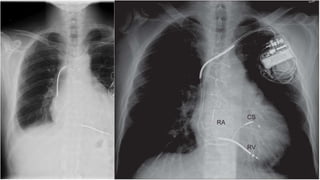

• #23 Paciente portador de ICD. TV fuera de rango de detección